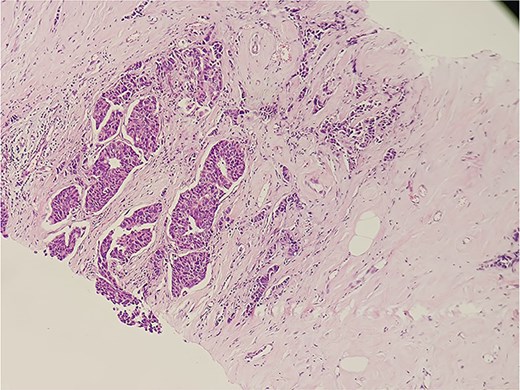

The patient was diagnosed with invasive carcinoma of the right breast (pT2N0, Stage IIA) and ipsilateral axillary lymph node tuberculosis. The patient underwent a right modified radical mastectomy (MRM) with axillary dissection. Histopathological evaluation of the breast specimen confirmed invasive carcinoma (Fig. 4). The resected margins and nipple-areola complex were free of tumor infiltration. Adjuvant chemotherapy was administered in six cycles (anthracycline-based regimen), followed by hormonal therapy with letrozole due to ER positivity. The patient received standard anti-tuberculosis therapy (ATT) for 6 months as per national guidelines. Subsequent PET-CT scans demonstrated a reduction in soft tissue thickening and no evidence of metabolically active disease, signifying a good therapeutic response. The axillary tuberculosis also resolved with ATT.

Histopathological slide section of biopsy specimen taken from the right breast lesion showing invasive ductal breast carcinoma, NOS, grade II based on the Nottingham grading system.